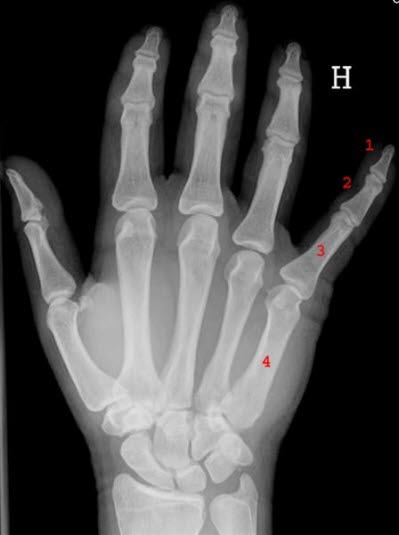

Brudd i skaftet i metakarpene forekommer hyppig, spesielt i 5. metakarp.

Ved undersøkelsen finnes hevelse. Trykk mot beinet utløser smerte. Det er også stukningsømhet på bruddstedet (f.eks. ved lett dunk mot knokene). I noen tilfeller foreligger rotasjonsfeilstilling - ved knyting av hånden vil fingeren krysse over nabofinger. Ved metakarpbrudd vil det ofte foreligge nedsatt bevegelighet i tilstøtende MCP-ledd.

Målet med behandlingen er å få satt bruddet pent på plass, stive det av og forhindre seinkomplikasjoner. Brudd som er uten rotasjonsfeilstilling og som ikke har andre større feilstillinger, behandles konservativt. I første, fjerde og femte metakarp aksepteres vinkelfeil på inntil 10-20°. Ja, i 5. metakarp kan feilstilling på opptil 45° aksepteres. I andre og tredje metakarp aksepteres en noe mindre vinkelfeil. Brudd med større feilstillinger opereres. Det samme gjelder brudd man ikke klarer å trykke tilfredsstillende på plass. Bennet-brudd behandles operativt.